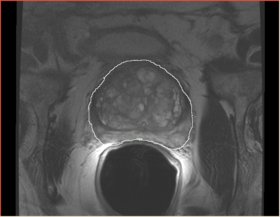

Prostate erMRI

After bias correction

Before - After subtract image

Recovered bias field